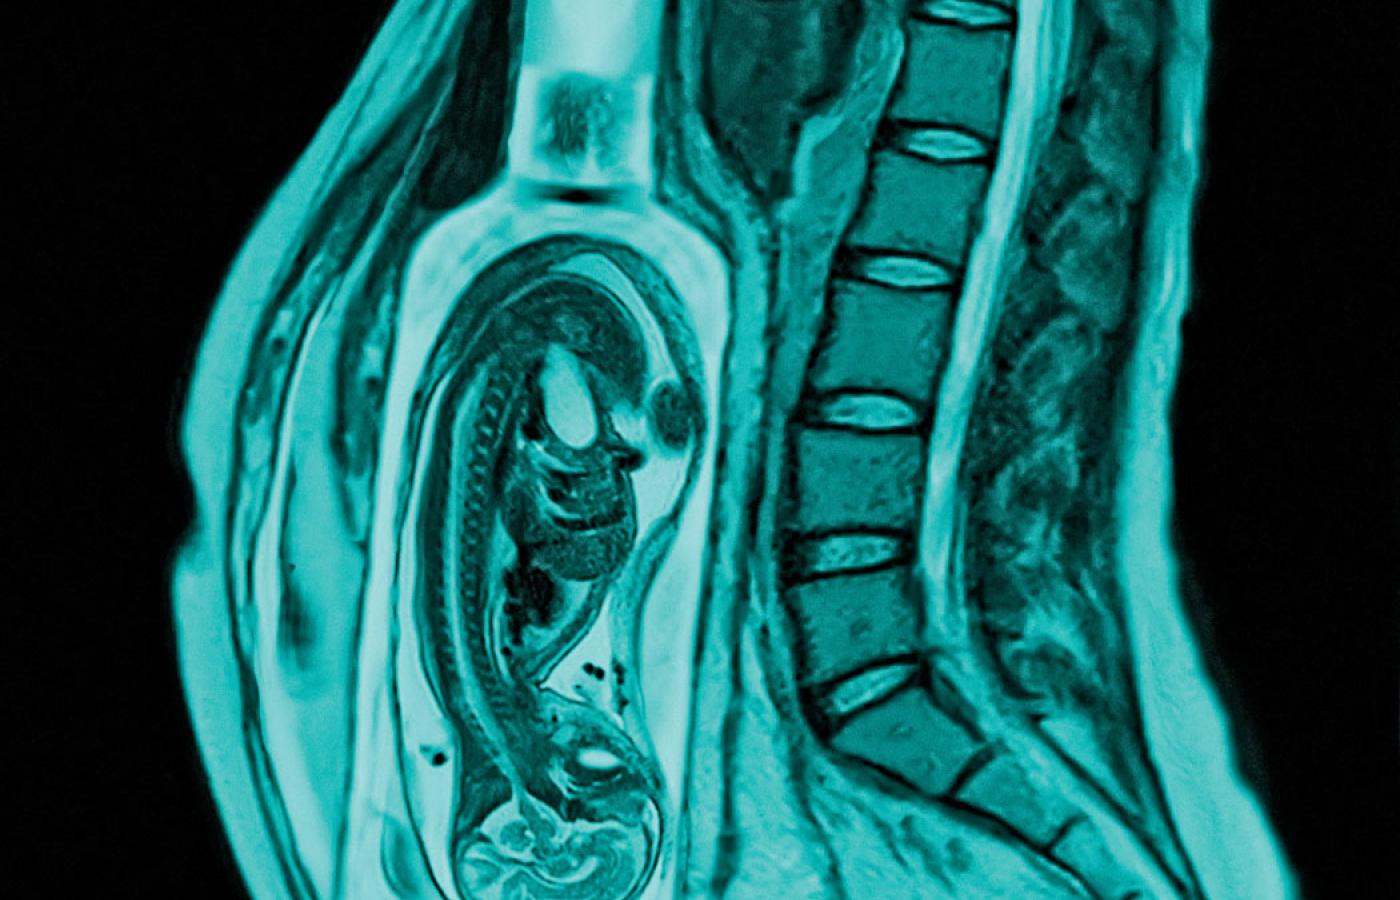

Dziewięć tysięcy. Tyle dzieci przychodzi na świat w Polsce w ciągu roku ze spektrum płodowych zaburzeń alkoholowych. Dziewięć tysięcy. Tyle dzieci przychodzi na świat w Polsce w ciągu roku ze spektrum płodowych zaburzeń alkoholowych. Igor Morski

Kruszynka ma dwa miesiące. FAS, czyli fetal alcohol syndrome, widać u niej na pierwszy rzut oka. Jest wcześniakiem. Mała główka, typowe oczy z krótką szparą powiekową, cienka górna warga i spłaszczona rynienka pod nosem. – Gdy patrzy się na dzieci z zespołem FAS, wszystkie są do siebie podobne, jakby były rodzeństwem – zauważa pani Jolanta. Kruszynka nie potrafi skoordynować ssania z połykaniem, więc trzeba ją karmić przez sondę. Picie mleka z butelki odpada. Nie reaguje na dźwięki. Kiedy podrośnie, ma przed sobą długie tygodnie rehabilitacji logopedycznej.